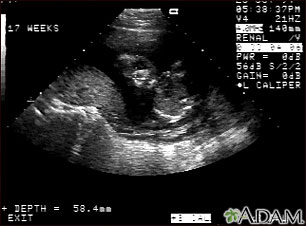

This is a normal ultrasound of the fetus performed at 17 weeks gestation. The fetal face can be seen in the middle of the screen. The head is tilted left toward the placenta, which can be seen as a mound in the left of the ultrasound image. Both eyes are visible, and the area of white within the eye is the lens. Other facial features, such as the nose and mouth, are also visible.